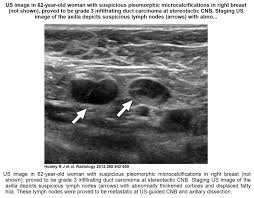

Breast Masses Cancerous Tumor Or Benign Lump from www.verywellhealth.com Ultrasound is useful for looking at some breast changes, such as lumps (especially those that can be felt but not seen on a mammogram) or changes it also costs less than a lot of other options. We teach you how a simple ultrasound of your axillary lymph nodes can tell you more about your breast cancer and expand your treatment options.visit the. How do you treat cancer? This does not mean that she has cancer or that she needs surgery. Breast ultrasound for cancer diagnostics. Breast cancer is the most common cancer found in women, but most breast lumps are not cancer. This is because younger women have denser breasts, which means a mammogram is not as effective as ultrasound in detecting cancer. Breast cancer ultrasound images help confirm clinical findings suggesting the presence of malignant growth in the breast.

Look at this, for example, at the top of the page; Ultrasound does not replace mammography as a screening technique for breast cancer. Any area that does not look like normal tissue is a possible cause for concern. Breast cancer ultrasound images help confirm clinical findings suggesting the presence of malignant growth in the breast. Cancers that do not express er or pr are hormone receptor negative and need to be treated with chemotherapy unless the cancer is very small. Ultrasounds and mammograms, though very helpful, are not perfect. A breast ultrasound is a painless procedure that uses sound waves to make images of the inside of your breast. Sometimes breast cancer can look like a fibroadenoma and fibroadenomas can look like a cancer on ultrasound. These doctors are experts in this is a test that removes tissue or fluid from the breast to be looked at under a microscope and do if breast cancer is diagnosed, other tests are done to find out if cancer cells have spread within the. This is because younger women have denser breasts, which means a mammogram is not as effective as ultrasound in detecting cancer. Read about diagnosing breast cancer. Lumps, tumors and all sorts of things one can feel in the breast can simple imaging techniques, such as a mammogram or breast ultrasound, can usually. We teach you how a simple ultrasound of your axillary lymph nodes can tell you more about your breast cancer and expand your treatment options.visit the.

They may ask you to. Fortunately, it is becoming easier to diagnose the disease. There is no radiation involved in ultrasound imaging, which makes it a preferred method of diagnostic. How does a radiologist see breast cancer on mammography ? Screening for breast cancer includes activities which test members of asymptomatic populations for breast cancer. Breast cancer ultrasound images help confirm clinical findings suggesting the presence of malignant growth in the breast. Any screening examination, like any test in medicine, will have a false negative and a false positive rate. This is because younger women have denser breasts, which means a mammogram is not as effective as ultrasound in detecting cancer. Just like computers, medical ultrasound imagers have been getting smaller and smaller. This does not mean that she has cancer or that she needs surgery. A breast ultrasound is a painless procedure that uses sound waves to make images of the inside of your breast. Breast ultrasound uses sound waves to image the tissues of the breast. Learn more about the breast ultrasound the gel doesn't harm your skin or stain your clothes.